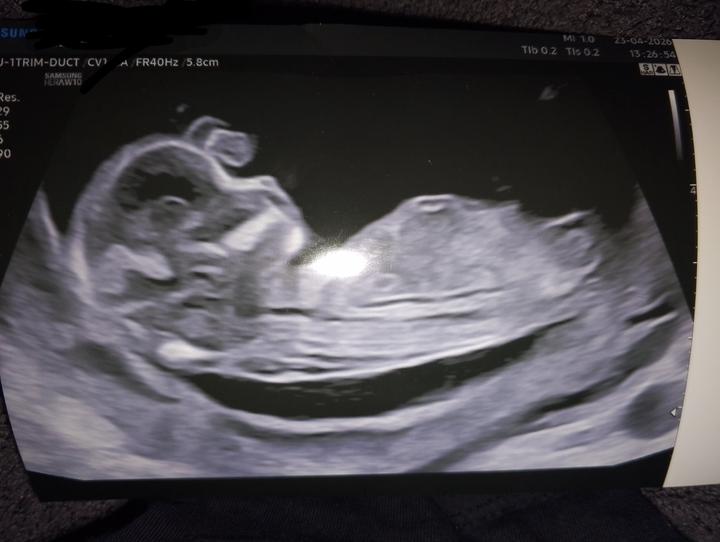

Kdo byl ted na 1 screeningu? A dozvěděl se pohlaví?

Ahojky pochlubte se svými fotografiemi z 1 screeningu? Ráda se podívám dozvěděli ste se už co čekáte?